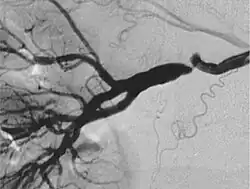

Wszystkie trzy typy mogą występować samodzielnie albo łącznie u jednego pacjenta. Klasyfikacja angiograficzna wyróżnia typ wieloogniskowy (multifocal type), z licznymi zwężeniami i obrazem „sznura pereł”, któremu w klasyfikacji histologicznej odpowiada typ z zajęciem błony wewnętrznej, typ cewkowy i typ ogniskowy, nie pokrywające się z klasyfikacją histologiczną.

| Klasyfikacja angiograficzna FMD | |||

|---|---|---|---|

| Typ I | Typ wieloogniskowy (multifocal type) | 62%[15] | ![]() |

| Typ II | Typ cewkowy (tubular type) | 14%[15] | ![]() |

| Typ III | Typ ogniskowy (focal type) | 7%[15] | ![]() |